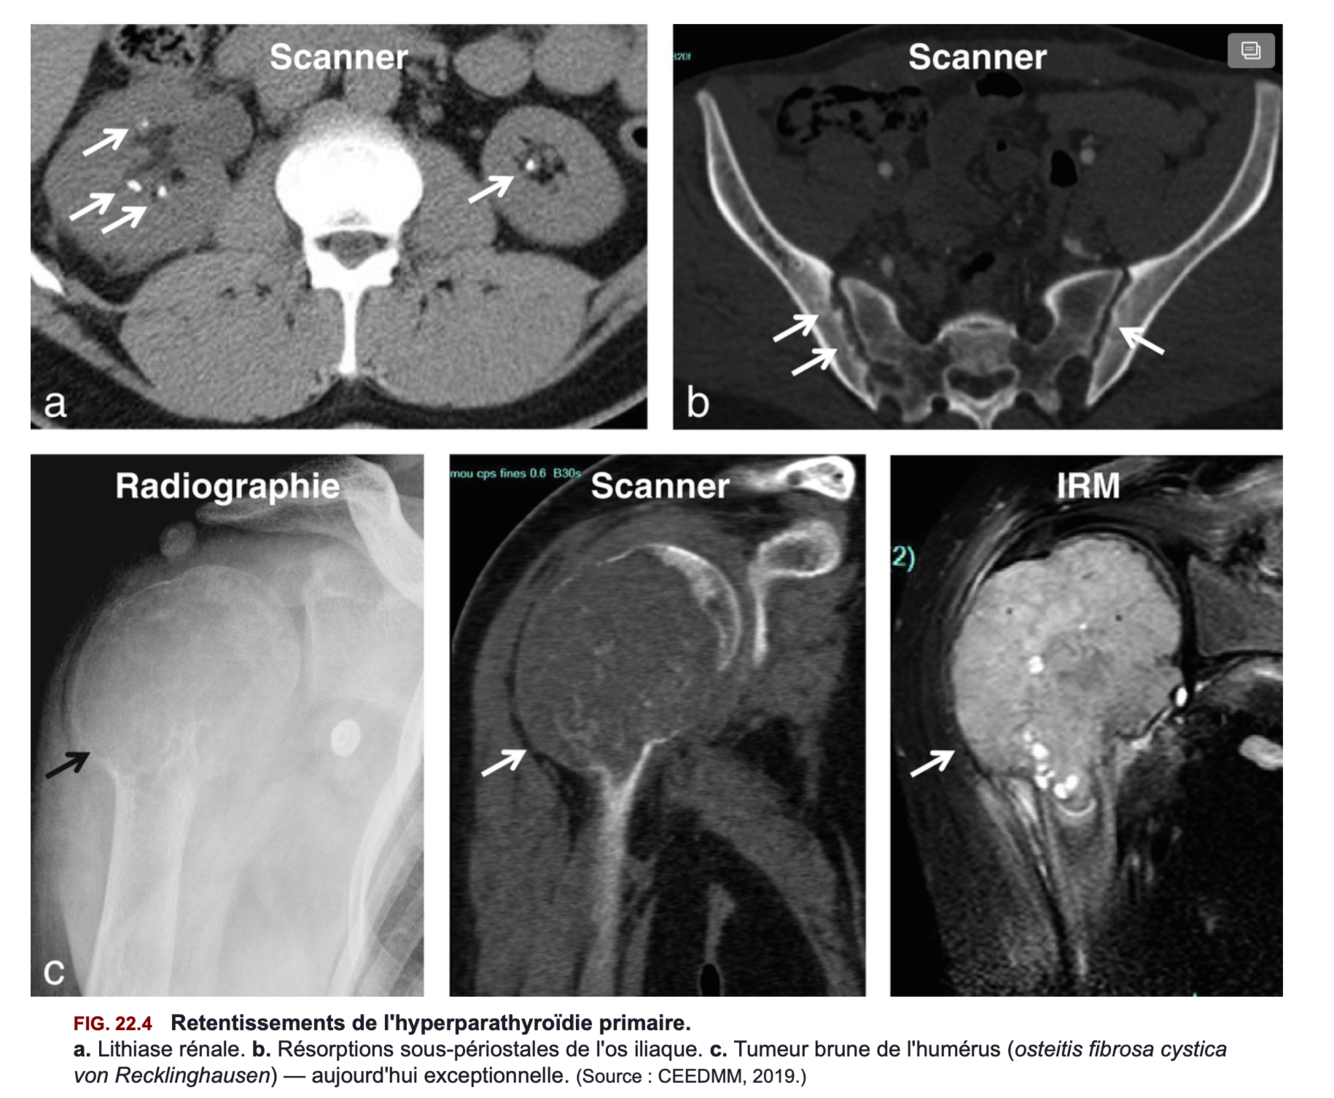

Signes cliniques de l’hyperparathyroidie primaire = (3)

= Souvent asymtomatiques mais parfois :

+ S’y ajoutent des signes osseux, rénaux et articulaires parfois révélateurs, qui constituent déjà des complications de la maladie

- Lithiases rénales = biatérales, récidivantes, radio-opaques et parlantes

+ La néphrocalcinose est aussi possible.

- Un syndrome polyuro-polydipsique modéré (de l’ordre de 3 à 4 litres par jour) fait partie du tableau clinique.Il s’explique par une réduction de la sensibilité du tubule rénal à l’action de la vasopressine en raison de l’hypercalcémie. Il s’accompagne d’un défaut d’acidification des urines qui contribue au risque d’infection urinaire et de lithiases.

- Des crises « pseudo-goutteuses » sont possibles, liées à la chondrocalcinose. Elles surviennent volontiers au niveau des poignets, des coudes, des genoux.

=> Figure 22.4

Signes radiologiques osseux de l’hyperparathyroidie = (7)

=> Fgure 22.4